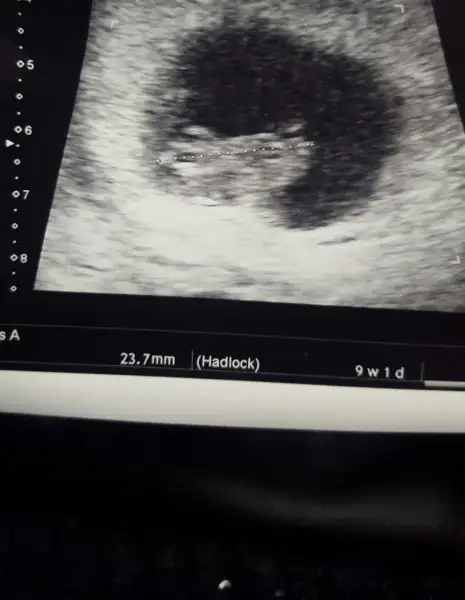

Tatlım cinsel organın ilk oluşumu gibi bişey :) genelde 9. Ve 8. Haftalarda görünüyor :) paralel olunca prenses ve daha acili olunca prens oluyormuş :)